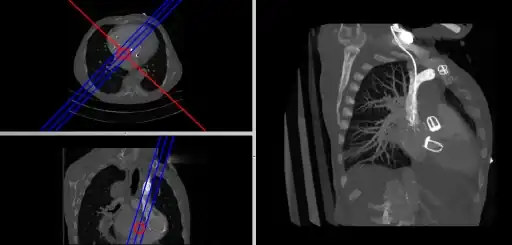

This form of image presentation is sometimes referred to as a TCS display – implying the viewing of Transaxial, Coronal and Sagittal slices. It can be combined with the slice projection methods we discussed earlier, as illustrated in the two sets of images below, where the blue lines highlight the limits of the coronal projections:

Axial and sagittal reconstructions from the SPECT lung-perfusion study with various coronal projections.

Axial and sagittal reconstructions from the CT study with a coronal MIP.

• Oblique Reconstruction

Oblique MPRs are possible by defining angled planes through the voxel data , as illustrated in the following figure:

CT MPR incorporating an oblique MIP.

Here the plane can be defined in, say, the axial images (red line, top left) and a maximum intensity projection (the limits used are highlighted by the blue lines), for example, can be displayed for the reconstructed plane (right). This technique is useful when attempting to generate perspectives in cases where the visualization of three-dimensional structures is complicated by overlapping anatomical detail.